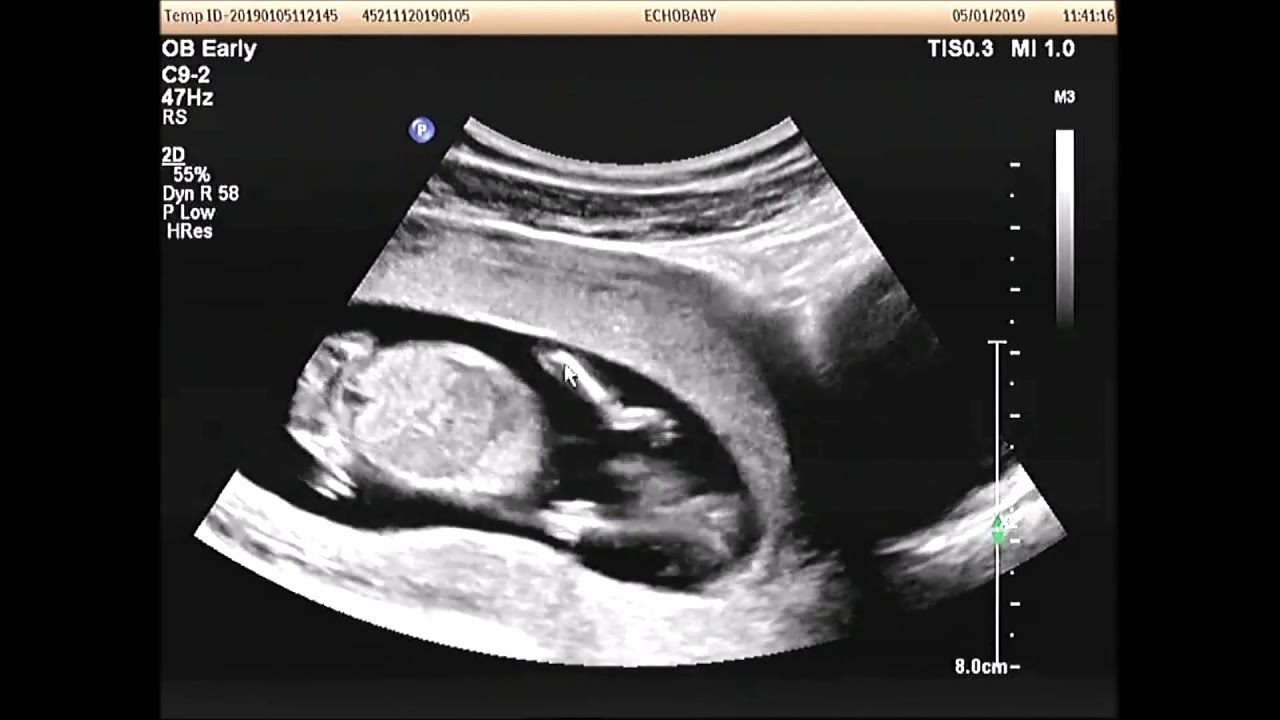

Rond de 10-13 weken krijg je een echo om te bepalen hoe lang je zwanger bent: de termijnecho.. Over de 13 wekenecho. Vanaf 12 weken en 3 dagen tot en met 14 weken en 3 dagen zwangerschap kun je een 13 wekenecho laten maken. De echoscopist kijkt met een echoapparaat naar de schedel, het hart, de buik, de armen en benen en de wervelkolom.. 13-weken echo. Vanaf 1 september 2021 is het mogelijk om de 13 weken echo te laten verrichten. De 13 wekenecho is, net als de 20 wekenecho, een onderzoek naar lichamelijke afwijkingen. De 13 wekenecho kan alleen plaatsvinden in de periode 12+3 tot en met 14+3 weken van je zwangerschap. Sommige (ernstige) afwijkingen zijn al te zien bij 13 weken.